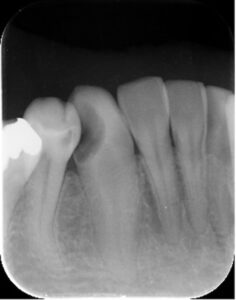

過去に根管治療をなされた患者様ですが、歯の根っこの先まで薬が詰まっておらず、細菌感染を起こして根っこの先に炎症(黒い部分)が出来ています。

古い詰め物、感染した根管内の歯質を除去しています。

歯の根の先まで薬を詰めて炎症の部分も小さくなっています。